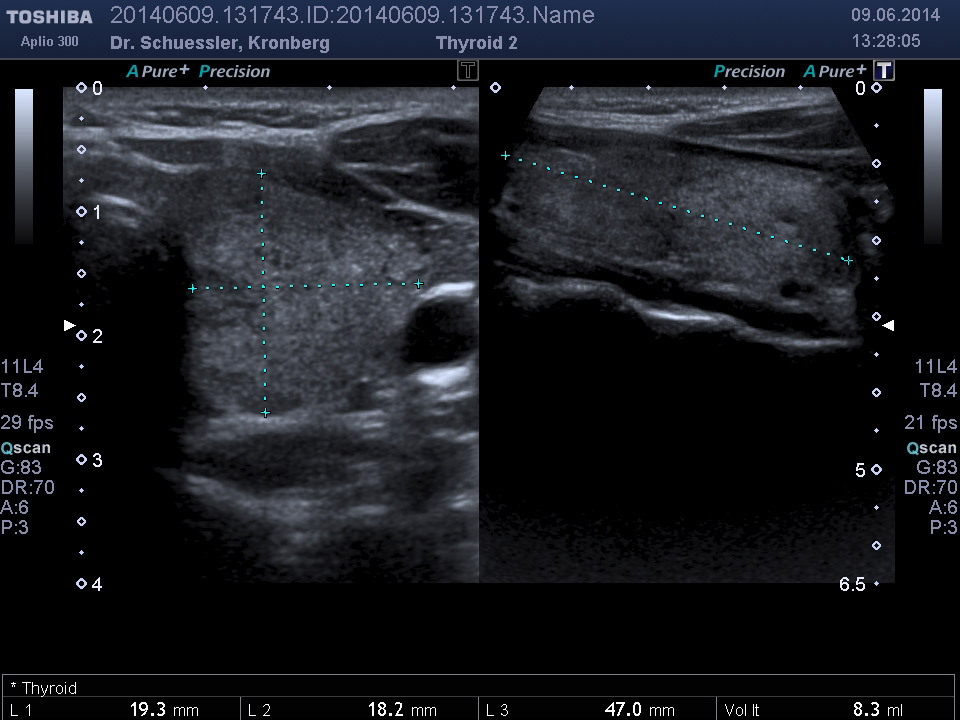

Farbkodierte Ultraschalluntersuchung der Schilddrüse

Mit dieser Untersuchung lassen sich die Schilddrüsengröße, ihre Struktur und auch Knoten, Zysten oder entzündliche Veränderungen sichtbar machen. Durch Hinzunahme der Farbkodierung lässt sich auch die Durchblutungssituation der Schilddrüse sichtbar machen.

Ultraschalluntersuchung am liegenden Patienten.